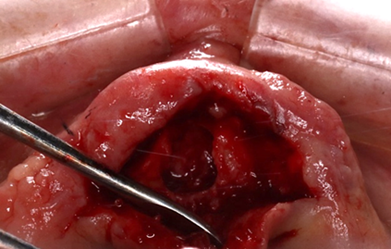

The treatment is done by complete enucleation of the cyst via palatal approach under local anesthesia. Palatal incision was performed and detachment of palatal mucosa in the region between the right and left canines approximately. Dissection was performed between the cystic capsule and the adherent mucosa, followed by cyst enucleation and cleaning of the cavity. The flap was sutured with 3/0 silk.

Figure 13: Occlusal view of the maxilla.

Figure 15: Incision and removal of the cyst.